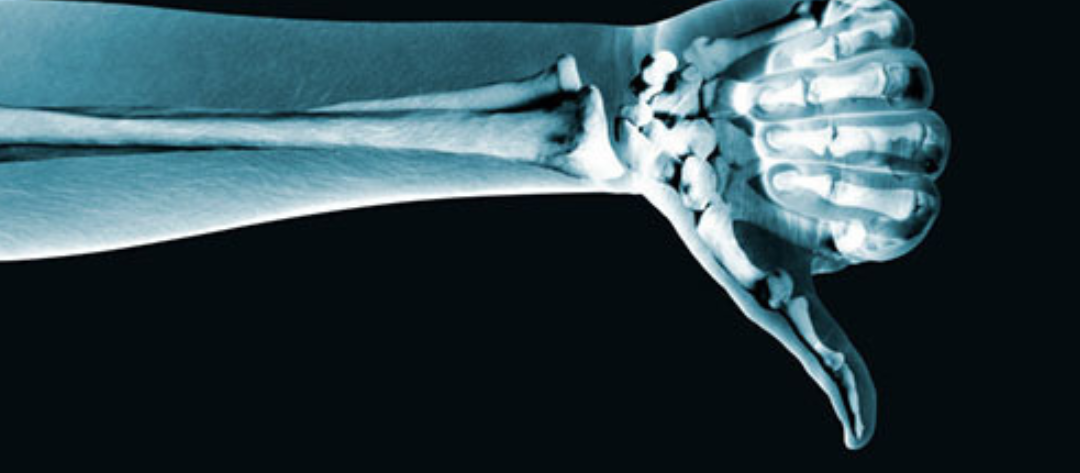

5 Reasons why you don’t always need an Xray, Ultrasound or MRI

Following an injury, patients often ask us “Do I need a scan?”, or delay coming to see us until they get one. Jay McGuinness argues that there are some very good reasons for NOT having X-rays or other expensive scans for the majority of injuries a Physio sees. Here’s 5 reasons you shouldn’t always have … Continue reading 5 Reasons why you don’t always need an Xray, Ultrasound or MRI